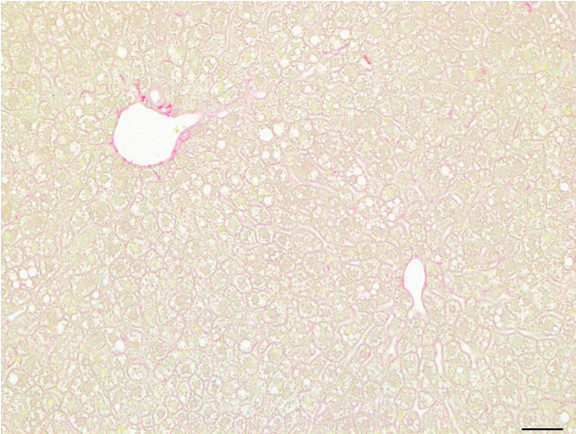

Figure 6: Histopathology for C57BL/6NTac mice placed on D09100310 diet (MASH B6NTac) or kept on chow diet (Control B6NTac) from 6 weeks of age. Animals were on diet for 27, 35 or 53 weeks. Hematoxylin and eosin (H&E) staining illustrates morphological changes including steatosis and infiltration of immune cells. Activated HSCs were identified in liver sections by using a rabbit polyclonal antibody to alpha-smooth muscle actin (a-SMA) (1:500 dilution; ab5694; Abcam, Cambridge, MA) which was detected by an anti-rabbit IgG embedded polymer with embedded horseradish peroxidase and visualized with 3,3′-diaminobenzidine (DAB) chromogen (Agilent, Carpentaria, CA). Hepatocellular lipid droplets were identified by visualization of the lipid-binding protein adipophilin known to be expressed in steatotic livers. Sections of livers were probed using a rabbit polyclonal anti-adipophilin antibody (1:200 dilution; NB110-40877, Novus Biologics, Littleton, CO) which was detected by an anti-rabbit IgG embedded polymer with embedded horseradish peroxidase and visualized with 3,3′-diaminobenzidine (DAB) chromogen (Aligent, Carpentaria, CA). Picrosirius red (PSR) staining illustrates collagen I and III fibers and is used to measure fibrosis. The same individual MASH or control animal is shown for all four stains in a particular time point. Different individual animals were used for each time point (i.e. data is not longitudinal by animal). Histopathology services provided by IDEXX BioAnalytics.